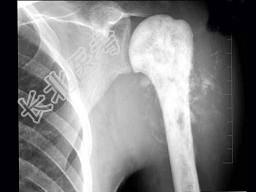

- 单项选择题男,28岁, 右肱骨上段肿痛1个月,疼痛以夜间明显, 摄片如图所示,提示骨肉瘤最为主要的征象是 ( )

A、溶骨性破坏

B、骨膜增生

C、肿瘤骨形成

D、软组织肿块影

E、Codman三角